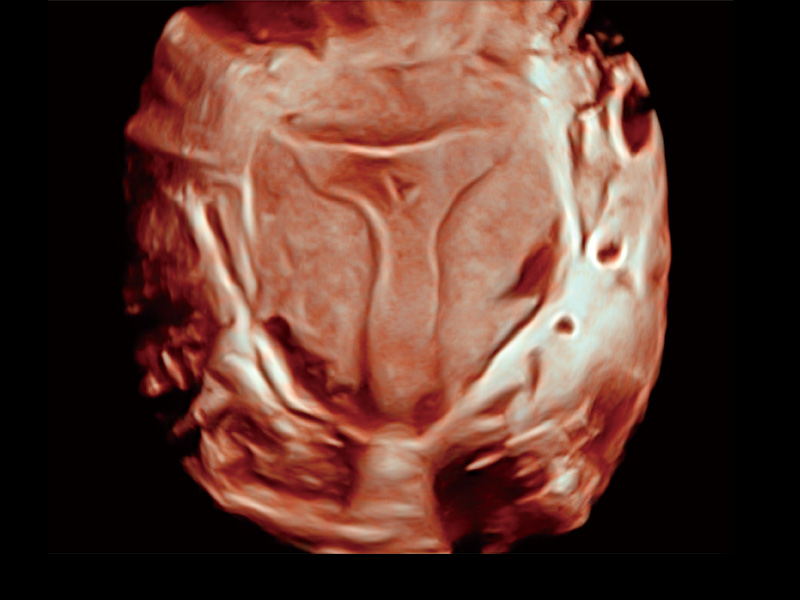

卵巢多囊样改变